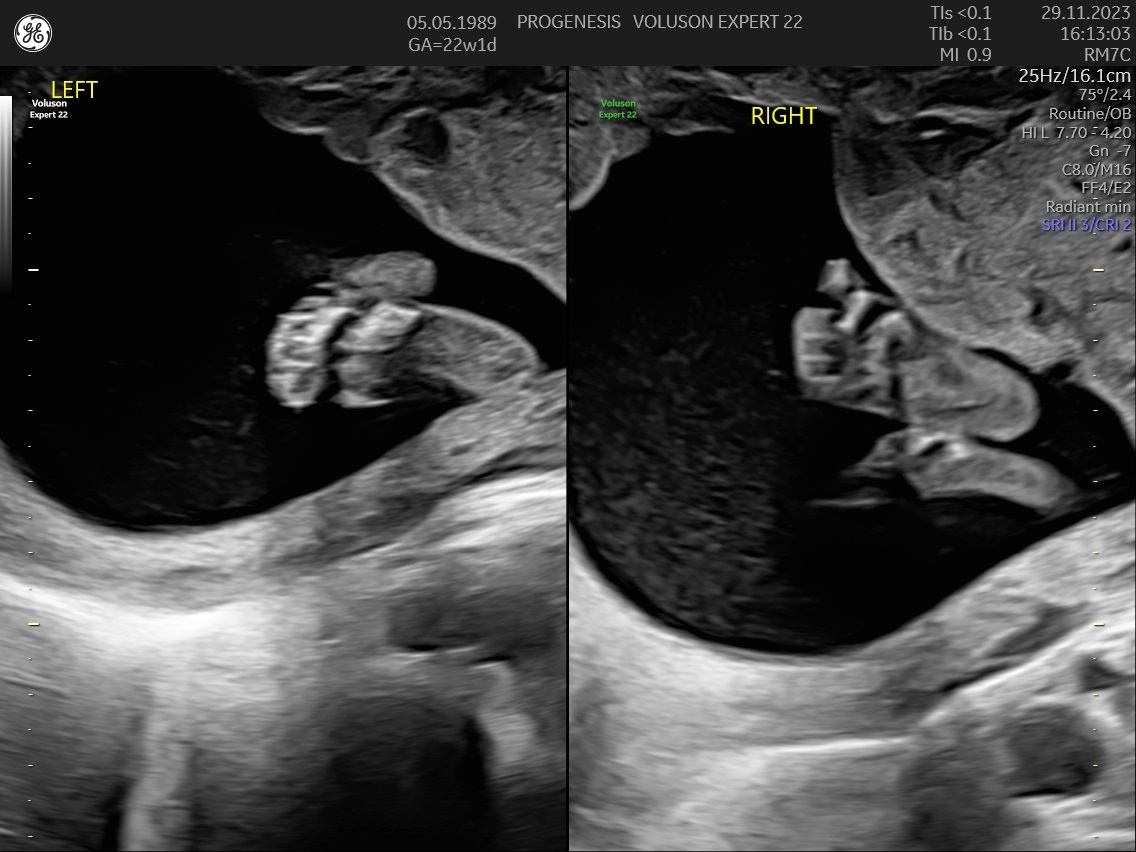

Υπερηχογράφημα Β΄Επιπέδου (20-24 εβδομάδων)

α) Η λεπτομερής αξιολόγηση της εμβρυϊκής ανατομίας, όπου αναγνωρίζονται τυχόν ανατομικές ανωμαλίες.

γ) Ο έλεγχος της ανάπτυξης του εμβρύου, του πλακούντα, του ομφαλίου λώρου και του αμνιακού υγρού.